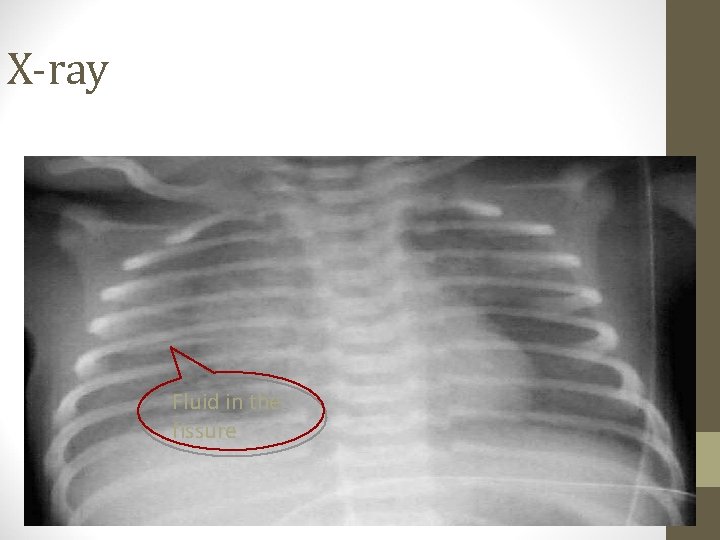

TTN • Tachypnea immediately after birth or within two hours, with other predictable signs of respiratory distress. • Symptoms can last few hours to two days. • Chest radiography shows diffuse parenchymal infiltrates, a “ wet silhouette” around heart, or intralobar fluid accumulation

X-ray Fluid in the fissure

Transient tachypnea of newborn • • • Term Cesarian delivery Usually tachypnea without O 2 requirment Resolve in 48 -72 houres Lung fluid X-ray